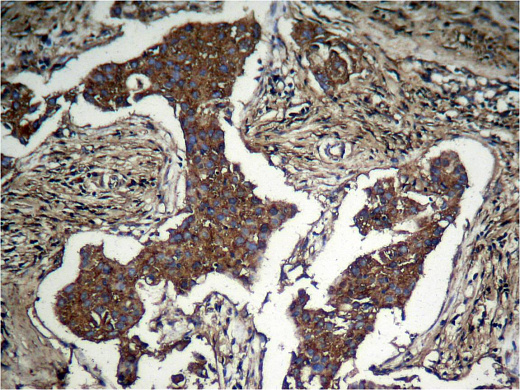

• применение – ICC/IF, IHC-P, WB;

Akt, также известная как протеинкиназа B (PKB), представляет собой серин/треонин-специфическую протеинкиназу, которая играет ключевую роль в клеточных процессах, таких как метаболизм глюкозы, апоптоз, пролиферация клеток, транскрипция и миграция клеток. AKT может фосфорилироваться комплексом mTOR 2 (mTORC2) и ДНК-зависимой протеинкиназой (DNA-PK) по остатку Serine 473 (Ser473).

• иммуноген – пептидная последовательность вокруг сайта фосфорилирования серина 473 (Q-F-S(p)-Y-S), полученная из человеческого Akt;